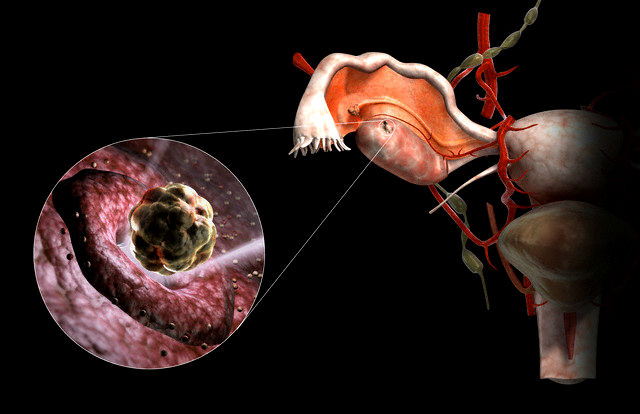

Заблуждения и факты о внутрибрюшной беременности